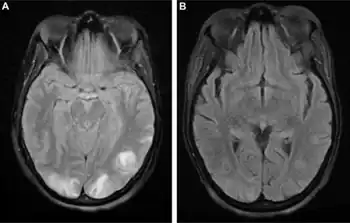

a) Cortical hyperintensity in posterior parieto-occipital lobe b)10 days after symptom onset shows resolution

There is no direct treatment for PRES, other than removing or treating any underlying cause. For instance, immunosuppressive medication may need to be withheld.[1][4] 40% of all people with PRES are unwell enough to require intensive care unit admission for close observation and treatment of complications.[2] Those with seizures are administered anticonvulsants.[1]